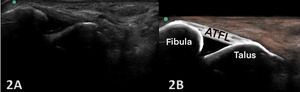

NORMAL VIEW IN OBLIQUE LONGITUDINAL AXIS (LAX): ANTERIOR TALOFIBULAR LIGAMENT (ATFL)

Figures 2A and 2B Oblique Longitudinal/LAX Axis View: Careful transducer placement spans the joint between the proximal fibula and the distal talus. The fibers of the normal ATFL will extend between the bony landmarks in a linear, uniform appearance. The ligament interdigitates with the deeper, anterior joint capsule and may APPEAR to dip into the joint space.